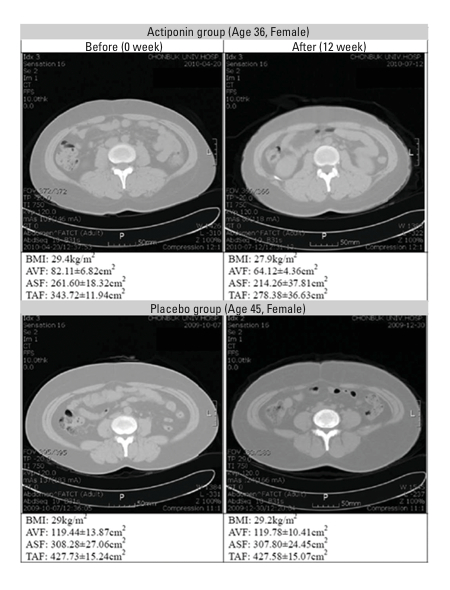

A programme of clinical work was subsequently initiated and the first of these, a study of the effects of ActivAMP, has been published in the prestigious journal Obesity.8 In this double-blind trial, 80 subjects with a BMI between 25 and 30 were randomised to active or placebo groups and treated for 12 weeks. The active group received capsules containing 450mg of ActivAMP per day. No recommendations were made regarding diet or exercise. At trial end, total abdominal fat area, body weight, body fat mass, per cent body fat and BMI were significantly decreased (p=0.044, p<0.05, p<0.0001, p<0.0001 and p<0.05, respectively) in the active group compared with the placebo group. Interestingly, the reductions in visceral adiposity were particularly marked, as they are following exercise (see Figure 2). No clinically significant changes in any safety parameter were observed.

Figure 2: Study of the effects of ActivAMP